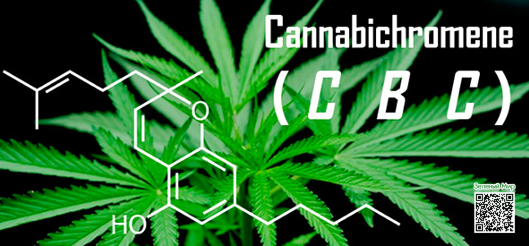

Что такое Каннабихромен, и с чем его едят? Это одно из активных веществ, которое обнаружили в каннабисе. Именно его стоит благодарить за противовоспалительный и противовирусные эффекты конопли.

Кроме того, CBC является важной составляющей для общего обезболивающего действия медицинской марихуаны, однако механизм его воздействия на организм еще недостаточно изучен, чтобы делать однозначные выводы. Молекулярная структура вещества подобна структуре других каннабиноидов, наиболее известные из которых: тетрагидроканнабидиол (ТГК), тетрагидроканнабиварин, каннабидиол и каннабинол.

Подробная информация о каннабисе и его свойствах стала доступнее, и многие уже знают, что воздействие производных продуктов растения на человека определяется количеством активных компонентов – каннабиноидов. Названия ТГК или каннабидиола в различных публикациях встречаются довольно часто, однако о таком компоненте, как каннабихромен, мало кто слышал.

Это печально, т.к. в действительности этот каннабиноид является вторым наиболее распространенным активным веществом каннабиса после ТГК. Другими словами, он встречается намного чаще, чем каннабидиол – самый известный не психоактивный компонент марихуаны. Казалось бы, производным продуктам с КБД уже досталась слава самых ценных с точки зрения медицины. Однако исследования последних лет доказывают, что каннабихромен может использоваться в терапевтических целях не менее эффективно. Тому есть несколько причин.